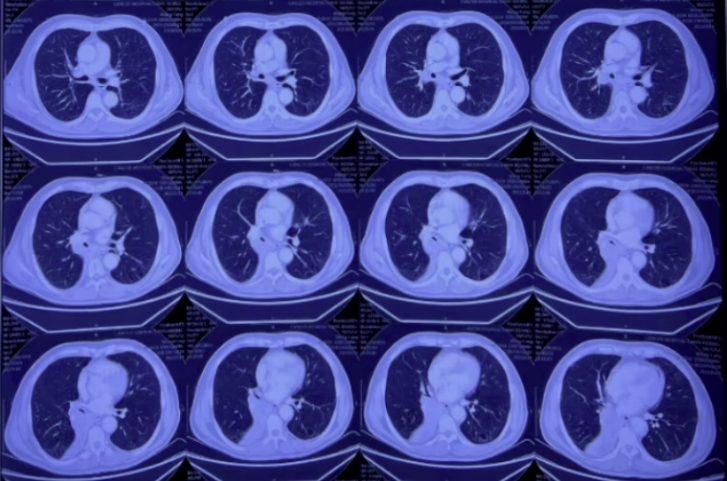

2022年1月28日复查胸部CT:双肺感染仍然较重,虽未完全吸收,但较前有好转(图11)。

图11 复查胸部CT(2022-01-28)

2022年2月18日胸部CT:双肺病灶较前进一步吸收,右下肺脓肿尚未完全吸收(图12)。

图12 复查胸部CT(2022-02-18)